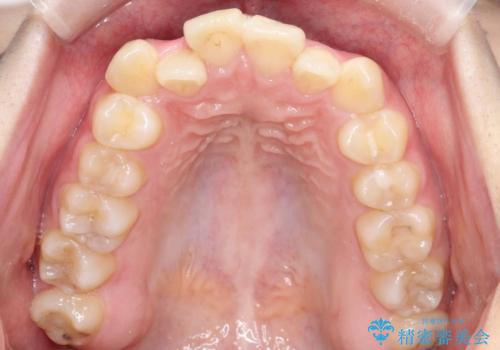

- 「歯のデコボコ、八重歯、口ボコが気になる」を主訴に来院された患者様です。

上下左右4番(4本)の歯を抜歯しワイヤー矯正で治療を行いました。

計4本の抜歯を行い、歯のデコボコと口元がすっきりし、大変ご満足していただけました。